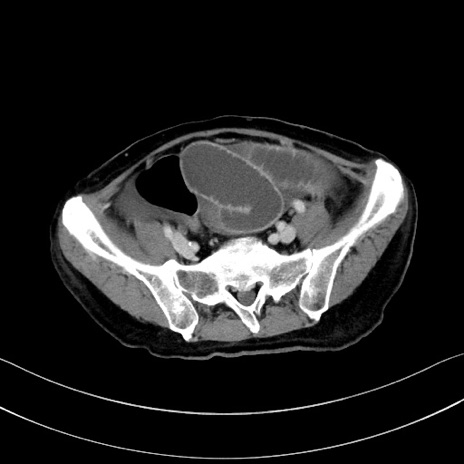

冠状断像